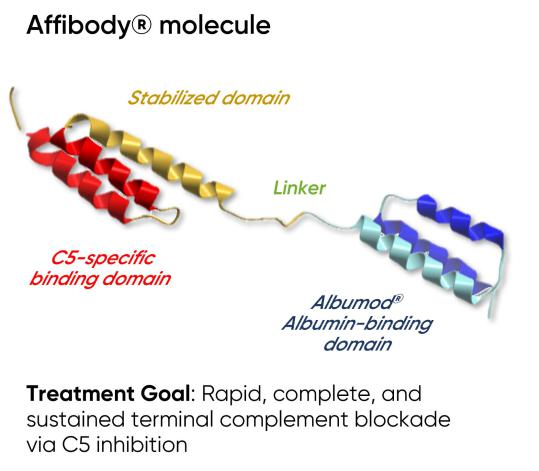

Our team has a track record of success in designing, developing, and securing marketing approval for C5 complement inhibitors, including Soliris and Ultomiris, for patients around the world with severe and rare complement-mediated diseases. Our most advanced product candidate in this therapeutic area is RLYB116, an inhibitor of C5, which is a central component of the terminal complement pathway. RLYB116 is an Affibody molecule attached to an albumin binding domain ("ABD") that has the potential to drive the rapid, complete, and sustained inhibition of C5 with a SC injection. We have completed a Phase 1 clinical trial in healthy participants that included the study of RLYB116 as both a single ascending dose (“SAD”) and a multiple ascending dose (“MAD”).

RLYB116 is an inhibitor of complement component C5, a component of the complement pathway which plays a central role in innate immunity as well as shaping adaptive immune response. Dysregulation of the complement pathway has been implicated in the pathogenesis of a growing number of diseases, making it an attractive target for therapeutic intervention. Antibody inhibitors of C5 have been successfully developed to treat diseases caused by immune dysfunction, including PNH, aHUS, refractory gMG and relapsing NMOSD. RLYB116 includes an Affibody molecule, which is an antibody mimetic protein that has a much smaller molecular weight than a traditional antibody and may also be easier and less costly to produce. In contrast to most C5-targeted antibody therapeutics that are administered intravenously or via daily injection, RLYB116 has the potential to be administered as a small volume, once-weekly SC injection. RLYB116 also includes an ABD, which may extend the half-life of the Affibody domain. In addition, amino acid substitutions that are part of RLYB116 are intended to enhance its stability. We view RLYB116 as a potential pipeline-in-a-product with disease areas under consideration including PNH, gMG and APS. We believe RLYB116 can address significant unmet needs for patients with these diseases by providing a potential treatment that is more accessible and patient-friendly than existing marketed products, including by reducing the frequency and improving the route of administration.

Our solution: RLYB116

RLYB116 is an engineered protein that includes an Affibody molecule and an ABD. We acquired rights to RLYB116 from Swedish Orphan Biovitrum AB (Publ) ("Sobi"). RLYB116 was designed for optimal C5 binding, increased stability, as well as a long half-life in serum. Potential benefits of RLYB116 include:

Affibody Scaffold and RLYB116 Structure